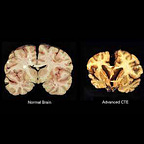

Their brains are being smashed against their skulls - which is what a concussion is - which ultimately causes CTE. Each concussion is a traumatic brain injury. And we have to stop making it sound like something other than what it really is.